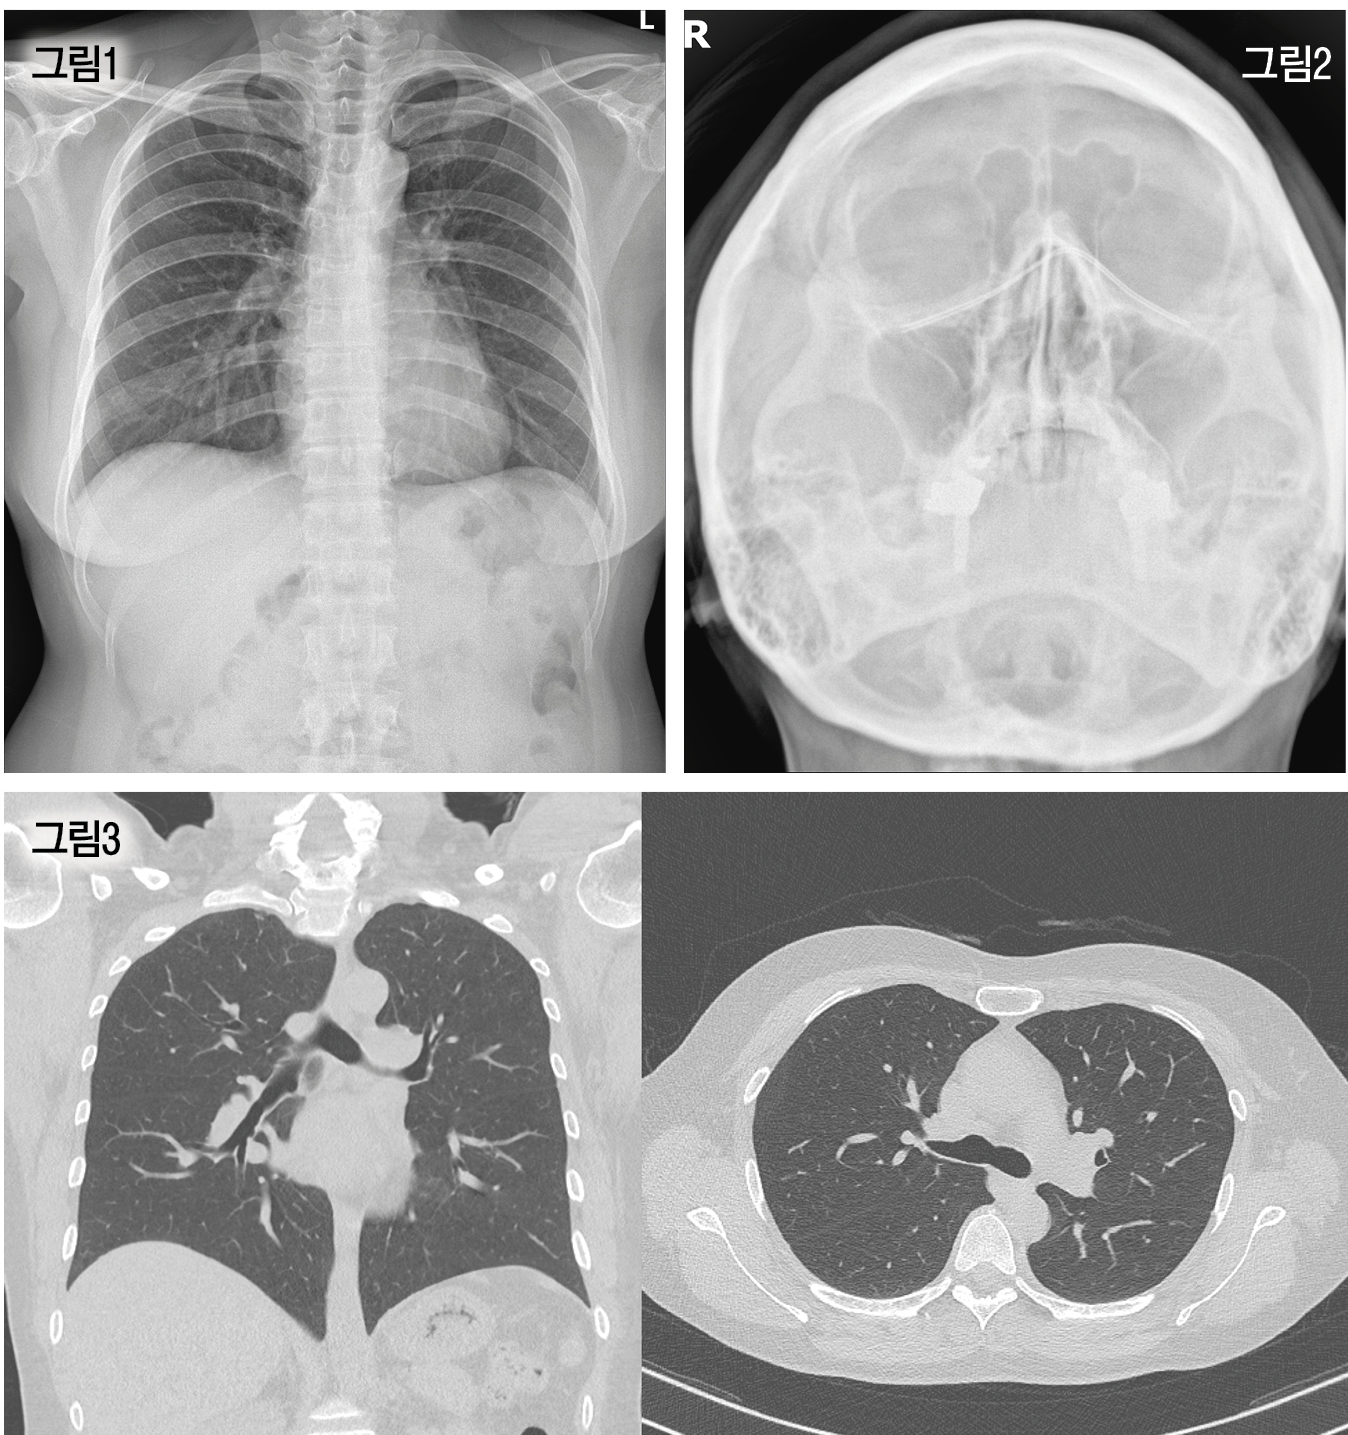

환자가 가지고 온 의무기록사본을 살폈다. Chest CT를 포함한 영상의학검사, 폐기능 검사를 시행했음을 알 수 있었다(그림 1,2,3). 하지만 이들 검사 결과에서 만성 기침의 원인이 될 수 있는 단서를 찾을 수는 없었다.

환자는 본원 내원 직전 또 다른 대학병원에서 혈액 검사, 객담 배양 검사를 시행했다. 의무기록사본을 발급하여 확인해 본 결과 혈액 검사, 객담 배양 검사와 함께 Chest CT, 폐기능 검사를 다시 시행했음을 알 수 있었고, 특별한 이상 소견은 관찰되지 않았다(그림 4).